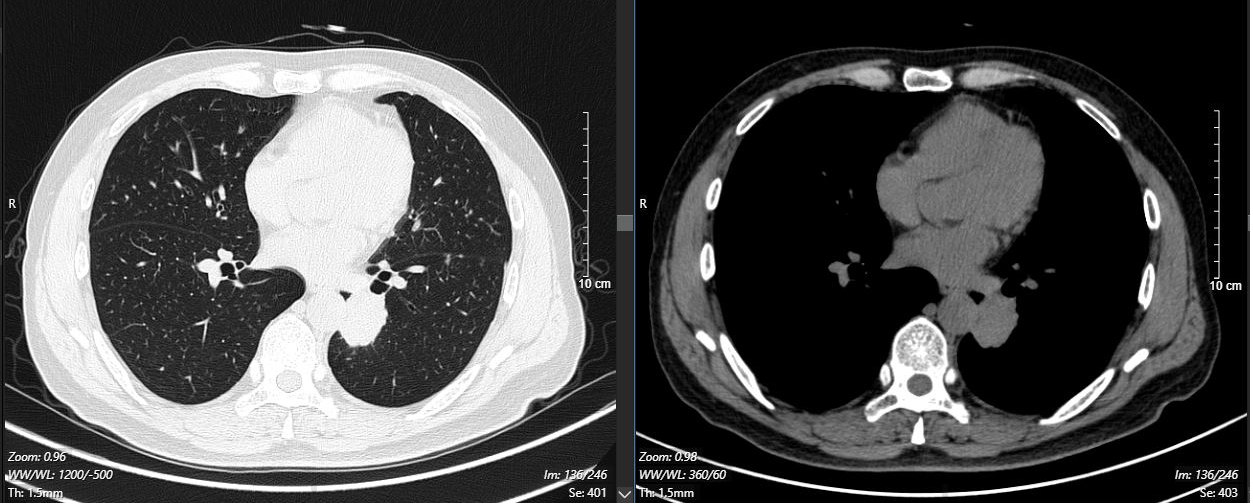

现病史:2024-11-18外院体检时行胸部增强CT示:两肺纹理增多,左肺下叶软组织密度影,大小约3.7*3.1cm,边缘见少许毛刺影,周围见少许斑片模糊影,左肺见多发结节影,最大径约9mm。左肺下叶占位,考虑肺癌,请结合纤维支气管镜及生化检查。左肺多发结节,肺内转移不排除。

2024-11-26 胸部CT检查示:

治疗5个月后(2025-05-07):复查CT显示左肺病灶显著缩小,达到PR,肺内结节明显吸收。